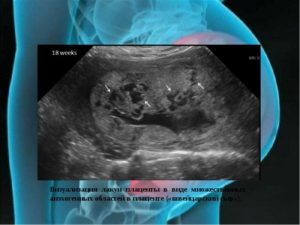

Структура плаценты неоднородная за счет расширения мвп

Главное, как функционирует плацента. Что касается неоднородности плаценты… Компенсаторные возможности плаценты велики. Структура плаценты с расширением МВП (межворсинчатые пространства).

Одной из распространенных особенностей изменения структуры является расширение МВП – межворсинчатых пространств в эмбриональном органе. Это место предназначено для обмена веществ между матерью и плодом.

Когда появляется необходимость в увеличении площади этого обмена, соответственно, расширяются и МВП.

Это явление не приводит к возникновению фетоплацентарной недостаточности, и обычно не требует дополнительных исследований.

- Структура плаценты с расширением МВП (межворсинчатые пространства). МВП называется место в эмбриональном органе, где между роженицей и плодом происходит обмен веществ. С развитием беременности ребенок требует все больше питательных веществ для своего роста и поддержки функций жизнедеятельности. Чтобы обеспечить его потребности происходит увеличение МВП. Расширение данного пространства не приводит к нарушению маточно-плацентарного кровотока, но и не исключает его. Дополнительные исследования при расширении МВП не проводятся.